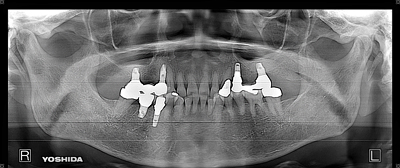

症例3【40代女性】右上74根尖病巣の治療 右上56 洞低膜を挙上しインプラント埋入

治療前

治療後(5年経過)

主訴 右上で物が噛めない。インプラントを希望され来院。

右上第二小臼歯はC₄にて抜歯。右上第一大臼歯は欠損の状態。

残存骨が5~6㎜程で、インプラント埋入には骨の高さが不足している為、ソケットリフト(骨造成)を行った。洞底膜を挙上することで、骨の高さの不足を解消。

採血のよるCGFメンブレンとAFGブロック(人工骨β‐TCPとAFGを混ぜたブロック)を填入しインプラント2本を埋入。約4ヶ月の免荷期間を経て、仮歯を装着、リハビリをし、約5ヶ月後にメタルボンド(金属焼付ポーセレン)を装着。

リスクとしては、ソケットリフト(骨造成)による一過性の副鼻腔炎が起きる可能性がある。まれに洞底膜が破れる可能性がある。ただし、膜は約3週で再生するので、膜の回復を待ち、再オペを行う。

費用 113万(オペ・ソケットリフト・人工骨・採血による濃縮血小板生成・仮歯・最終補綴物まで含む)